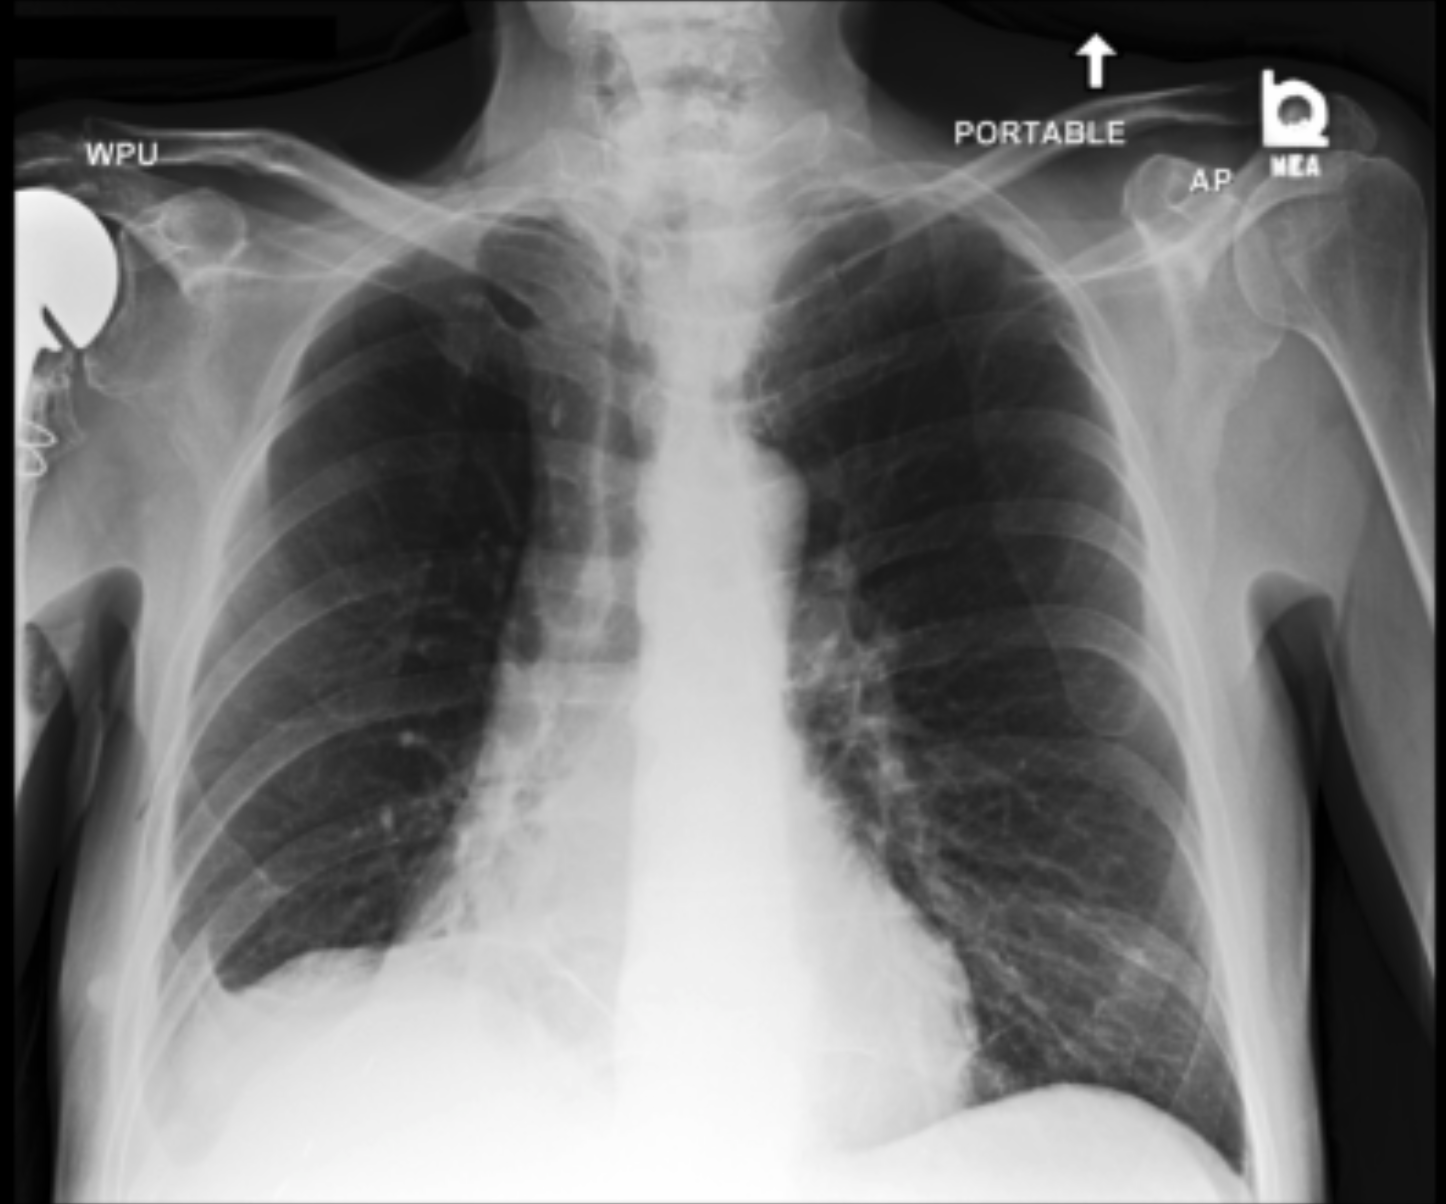

4.3.3 Visual grounding

In this section, we evaluate RadVLM’s visual grounding capabilities, which could help clinicians localize specific regions or pathologies on a CXR. This is particularly useful once a pathology has already been identified – either by a radiologist’s input or through our previously described AI tasks – since it allows one to pinpoint exactly where the abnormality appears on the image.

We report performance metrics for the three main grounding tasks RadVLM was trained on: anatomical grounding using the Chest Imagenome test set, abnormality grounding using the VinDr-CXR test set, and phrase grounding using the MS-CXR test set (Table 1). For each task, we use mean Average Precision (mAP) as our primary evaluation metric.

As mentioned in Table 2, some of the CXR-specific VLMs already have grounding capabilities. CheXagent was trained to handle both abnormality and phrase grounding tasks, while MAIRA-2 – originally trained to produce radiology reports with grounded observations – is also capable of predicting bounding box coordinates when provided with input text. After retrieving each model’s instruction template for generating bounding box coordinates (Appendix 1-Table 2), we evaluated both CheXagent and MAIRA-2 on all three grounding tasks performed by RadVLM.

Our results show that RadVLM performs well at localizing anatomical regions (e.g., “right lung”, “aortic arch”, illustrated in Figure 5a), achieving a mAP of 85.8 %, by far surpassing the other CXR grounding models (Table 4). This advantage is partly explained by including the Chest Imagenome dataset (and thus the anatomical grounding task) in the training set, which CheXagent and MAIRA-2 did not leverage. However, it remains a key feature for any grounding model to possess a fine-grained understanding of CXR anatomy.

For the abnormality grounding task, RadVLM is less consistent (Figure 5b), likely due to higher sparsity of abnormality locations and labels, yet it still achieves best performance (Table 4). For the phrase grounding task, while MAIRA-2 and CheXagent demonstrate great performance, RadVLM surpasses them with a mAP of 81.8% (Table 4), presumably benefiting from the newly released PadChest-GR dataset (Castro et al.,, 2024) used for training.

Overall, these results show that our instruction tuning strategy for visual grounding (covering three essential tasks), combined to a modern VLM backbone, offers a promising avenue to help clinicians localize anatomical and pathological features during a CXR exam. Furthermore, providing fine-grained details within an LLM-generated output may also enhance the ability to answer grounded questions in a multi-turn setting, as we explore next.

a. Anatomical grounding

silhouette

junction

structures

lung

abdomen

mediastinum

arch

b. Abnormality grounding

thickening

fibrosis

enlargement

lung disease